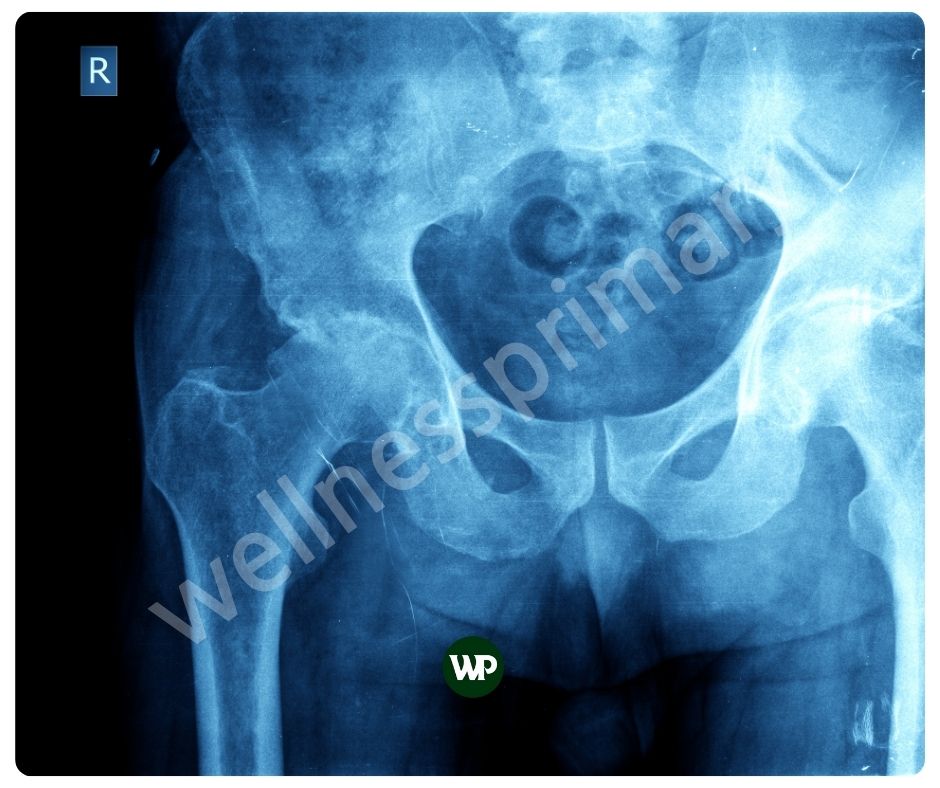

비타민K2 효능은 칼슘을 뼈에 결합시키는 데 중요한 역할을 합니다. 이는 뼈의 강도와 밀도를 증가시켜 골다공증과 같은 뼈 관련 질환을 예방하는 데 도움이 됩니다. 비타민 K2는 오스테오칼신이라는 단백질을 활성화시켜 칼슘이 뼈에 적절히 축적되도록 합니다. 이는 특히 폐경 후 여성과 노인에게 매우 중요합니다.